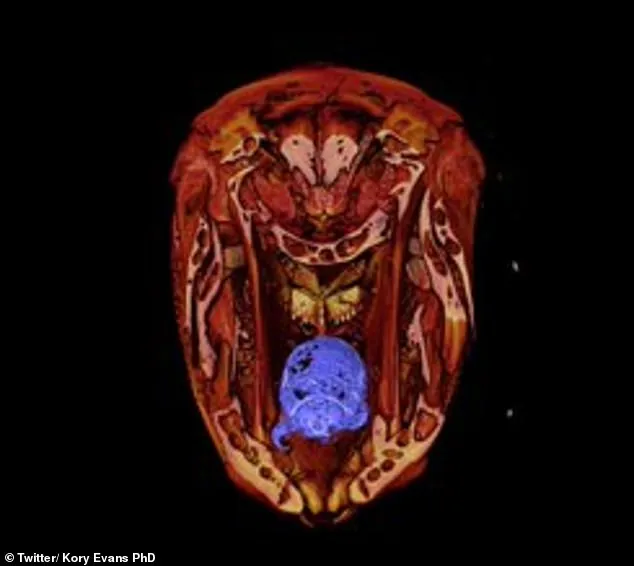

ขณะเดียวกันสื่อต่างประเทศได้รายงานถึงผลงานศึกษาของนักวิทยาศาสตร์ที่ทำการศึกษาปลาที่มีก้านครีบชนิดหนึ่ง ก็ได้พบว่ามีปรสิตเข้ามาแทนที่ลิ้นของมัน จากภาพเอ็กซ์เรย์ของกะโหลกศีรษะจะเห็นว่ามีสิ่งมีชีวิตตัวเล็ก ๆ อยู่ในปาก โดยเจ้าตัวประหลาดนี้จะเกาะอยู่ที่ลิ้นของปลา

จากนั้นมันก็จะค่อยๆกินเลือดที่ไหลออกมา จนกระทั่งโตขึ้นเรื่อยๆจนลิ้นของปลาฝ่อลงเนื่องจากขาดเลือด จากนั้นมันจะเอาตัวเองติดกับกล้ามเนื้อลิ้น และอยู่แทนที่ลิ้นไปโดยปริยาย โดยปลาจะใช้เจ้าปรสิตนี้ได้เหมือนลิ้นปกติ

จากข้อมูลทราบว่า แมลงปรสิตนี้ถูกเรียกว่า แมงกินลิ้น หรือ เหาปลา เห็บปลา (ymothoa exigua) เป็นปรสิตจำพวกกุ้ง-กั้ง-ปูในวงศ์ Cymothoidae มีความยาวตั้งแต่ 3 ถึง 4 เซนติเมตร ถือเป็นสัตว์กาฝากเพียงชนิดเดียวจากจำนวนหลายสายพันธุ์ ที่สามารถเข้าไปอยู่อาศัยแทนที่อวัยวะของโฮสต์ได้